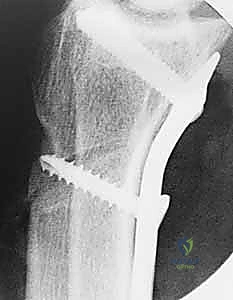

- الأشعة السينية (X-Rays): وهي الخطوة الأولى. تساعد الأشعة السينية في رؤية التغيرات في كثافة العظم الهلالي (المرحلة الثانية)، أو رصد أي انهيار في العظم (المرحلة الثالثة)، وكذلك تقييم طول عظمي الكعبرة والزند لاكتشاف وجود "تباين زندي سلبي".

- التصوير المقطعي المحوسب (CT Scan): يُستخدم أحياناً للحصول على صور ثلاثية الأبعاد وعالية الدقة للعظم الهلالي لتقييم مدى الانهيار والتفتت بدقة بالغة، مما يساعد الدكتور هطيف في التخطيط الجراحي الدقيق قبل العملية.

| تقصير عظم الكعبرة (Radial Shortening) | تقصير الكعبرة بمقدار 2-3 ملم لتخفيف الضغط عن العظم الهلالي وتوزيع الأحمال. | المراحل II و IIIA مع وجود تباين زندي سلبي. | ممتازة جداً، تخفف الألم وتوقف تطور المرض بشكل فعال. |